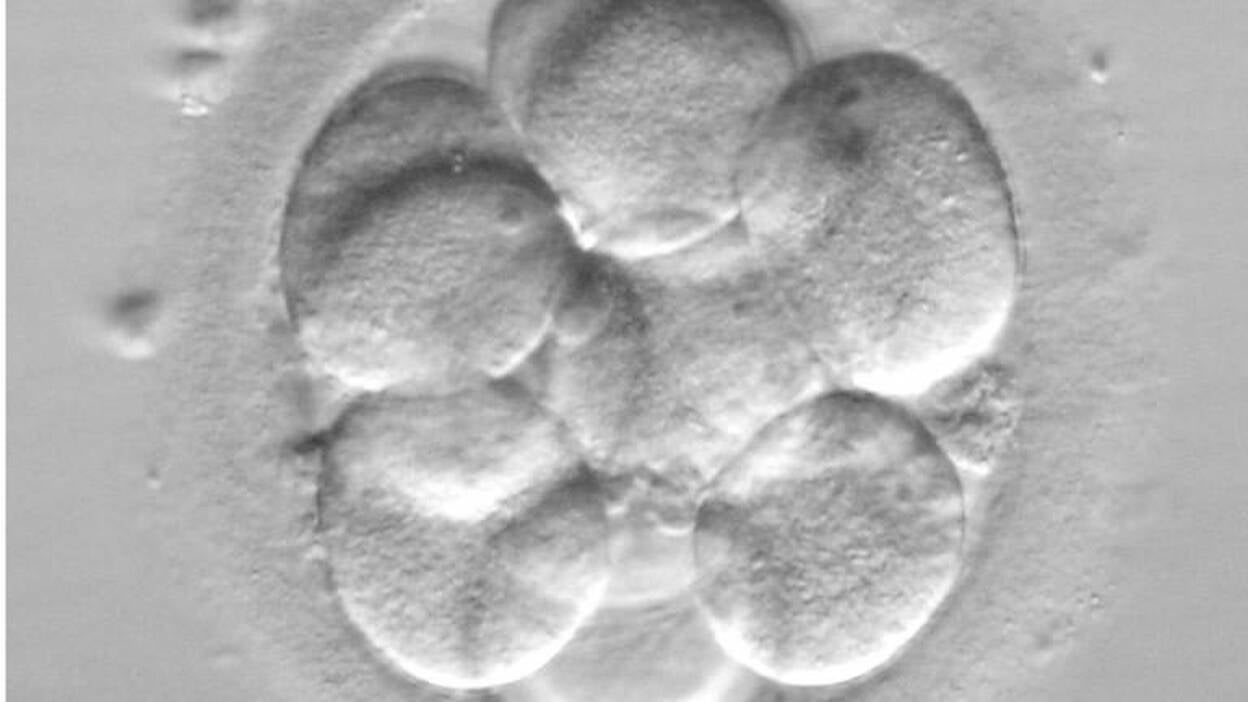

La Autoridad de Embriología y Fertilización Humana (HFEA) del Reino Unido concedió por primera vez a un grupo de científicos británicos el permiso para modificar genéticamente embriones humanos.

La investigación se llevará a cabo en el Instituto Francis Crick de Londres, que solicitó la licencia en septiembre de 2015, y tiene como objetivo proporcionar un mayor entendimiento sobre los primeros momentos de la vida humana.

La HFEA del Reino Unido indicó este lunes, en un comunicado, que los experimentos se desarrollarán durante los primeros siete días después de la fertilización y que podrían arrojar luz sobre los abortos.

Los investigadores han recalcado que no permitirán que los embriones cumplan su ciclo de crecimiento, sino que los estudiarán en las primeras etapas del desarrollo antes de destruirlos.

El equipo de científicos utilizará una tecnología conocida como CRISPR/Cas9 para cambiar los genes y estudiar así los efectos de estas variaciones en el desarrollo del embrión.